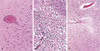

37

Identify what this and describe the histology

Cerebral ischaemia Infiltration of infaction by neutrophils at edges of the lesion where there is intact vascular supply Infarction has macrophages (middle pic)